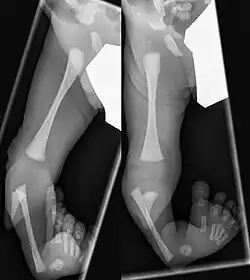

Eine Tibiale Hemimelie oder ein Tibialer Längsdefekt bezeichnet das angeborene Fehlen (Aplasie) oder die Unterentwicklung (Hypoplasie) der Tibia. Sie kann isoliert, häufiger aber in Verbindung mit Fehlbildungen am Fuß medial sowie einer Varusstellung im Rückfuß einhergehen.[1]

Einteilung

Für die Behandlung gebräuchlich ist die Klassifikation nach Kalamchi und Dawe:[6]

- Typ I Aplasie der Tibia, Fuß adduziert, + eventuell fehlende Strahlen medial

- Typ II Tibia nur distal fehlend, Artikulation zum Femur erhalten

- Typ III Dysplasie der Tibia distal mit tibiofibulärer Diastase (Fehlanlage der Sprunggelenksgabel)

Bei etwa 30 % tritt die Hemimelie beidseitig auf.[2] Nur bei 50 % ist der Fuß normal angelegt, meist fehlen mediale Strahlen des Fußes, Knochenkerne des Rückfußes sind fusioniert (Sprungbein#Fehlanlagen)[7]

Bereits im Mutterleib kann während einer Ultraschalluntersuchung die Fehlbildung erkannt werden,[2] die Verkürzung und Fehlstellung des Unterschenkels ist nach der Geburt offensichtlich. Ein Röntgenbild kann das Ausmaß der Fehlbildung sowie zusätzliche knöcherne Veränderungen dokumentieren. Mittels Sonographie können die knorpeligen Anlagen und deren Stellung zum Gelenk sicher dargestellt werden, wesentlich bei den Typen II und III.